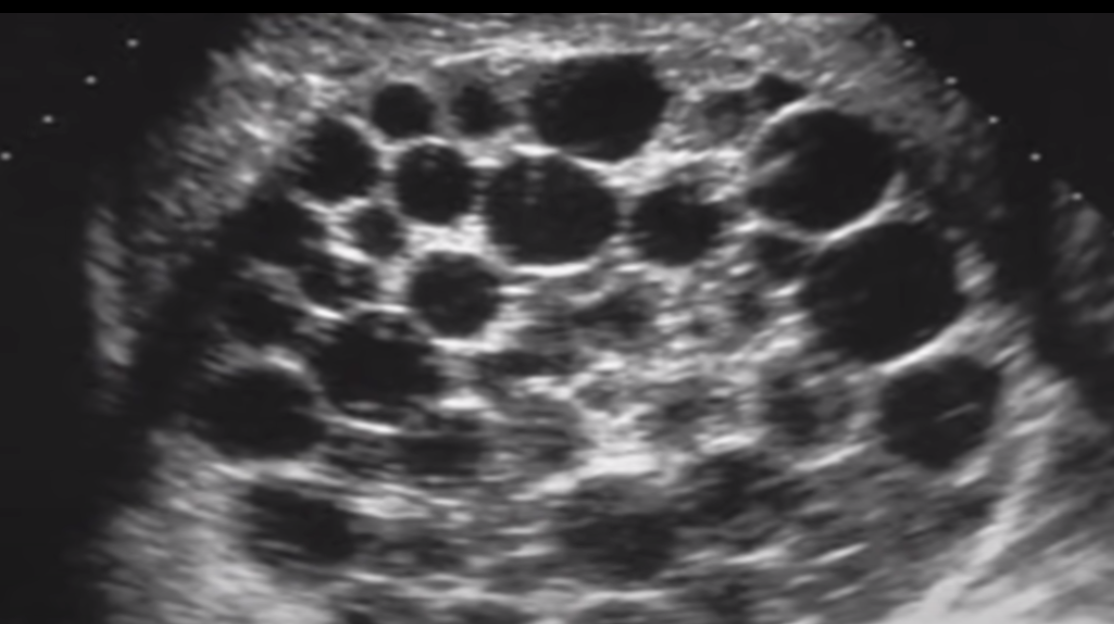

Describe: Echinococcus (4)